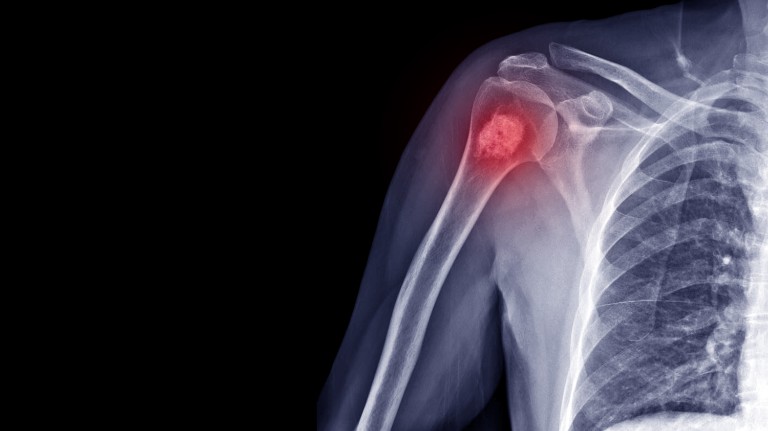

orthopedic oncology bone cancer imaging

Orthopedic oncology is a specialized field of medicine focused on the diagnosis, treatment, and management of tumors affecting the bones, joints, and surrounding soft tissues (muscles, tendons, ligaments, nerves, and blood vessels). These tumors can be benign (non-cancerous) or malignant (cancerous), and require a multidisciplinary approach involving orthopedic oncological surgeons, medical oncologists, radiation oncologists, radiologists, and pathologists to provide the best possible care.

Early diagnosis and treatment are crucial for improving outcomes in orthopedic oncology. Your doctor can perform a thorough examination, order imaging tests (such as X-rays, MRI, CT scans, and bone scans), and potentially recommend a biopsy to determine the nature of the tumor. If a tumor is suspected, referral to an orthopedic oncologist is essential for specialized care and treatment planning.